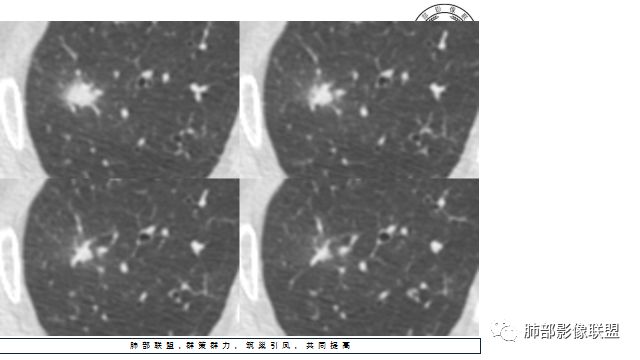

4.增强扫描成明显环形强化,中央液化坏死,内壁清楚且较为规整。

1.肺鳞癌是容易坏死,但如此小的结节出现影像明显可见的坏死区,且内壁如此清楚规整,我们临床实践中肿瘤非常少见,重要的事情说三遍!!!

病灶缺乏典型的分叶且明显可见的坏死区,腺癌就更为罕见。

2.病灶周边可见薄晕,会想到隐球菌感染,可以出现空洞,但内壁如此清楚的空洞少见。

好发于肺尖或尖后段胸膜下的密度不均的结节什么病最常见?结核!

小病灶常常出现空洞的什么病最常见?结核!

空洞内外壁都很清楚的什么病最常见?结核!

周围伴随小结节及条索影的什么病最常见?结核!